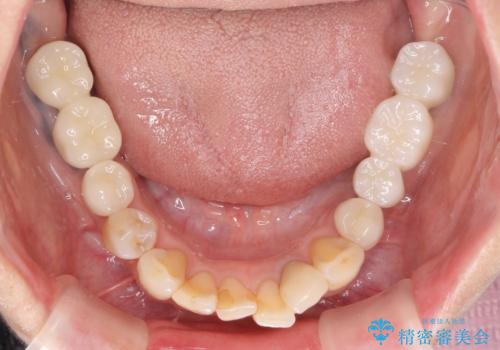

全顎的 虫歯治療 インプラント補綴

- 「他院で虫歯治療を行っているが、延々終わらず数年経過している。全体的な治療を希望したい。」と全顎的な治療を希望され来院されました。

・再発した虫歯

・銀歯の下にできた虫歯

・根尖性歯周炎

・残根状態の歯

など、虫歯を原因とする問題が多発した状態です。

今後延々と治療を繰り返さないために、全ての銀歯を外し虫歯を丁寧に取り切り、根管治療を行い、残せない歯は抜去を行った上でインプラント治療を行っていくことで全体的な治療を計画していくこととなりました。

工程数が多かったため治療期間はかかりましたが、しっかりと安定した噛み合わせ、審美的な口腔内環境を達成することができ大変満足していただくことができました。